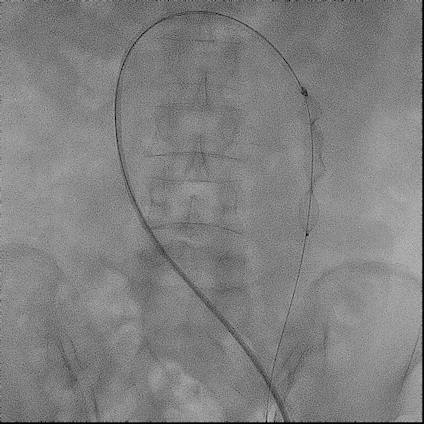

手术过程(二):

使用“Wire In Plug” 技术:在体外释放 20 mm AVP Ⅱ (网盘不解锁),使用穿刺针配合stiff导丝穿过三个网盘,回收至鞘内。